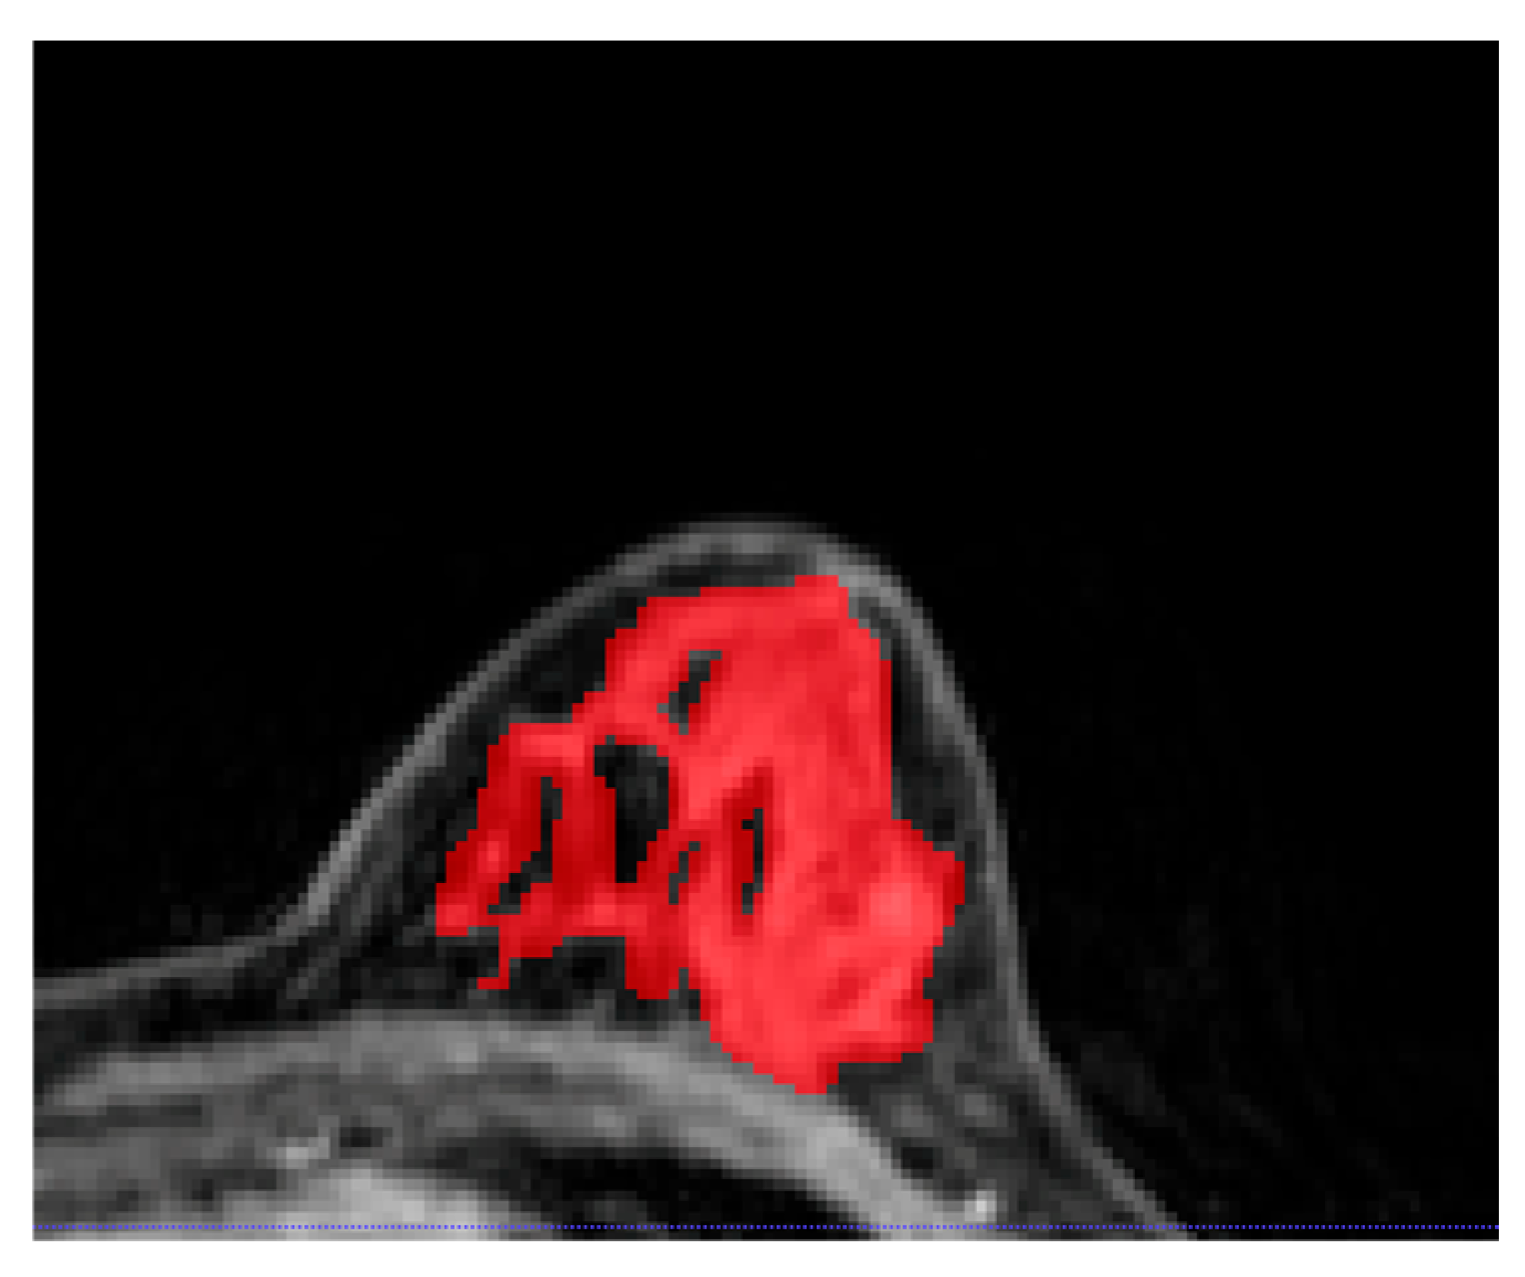

2.4. Image Segmentation